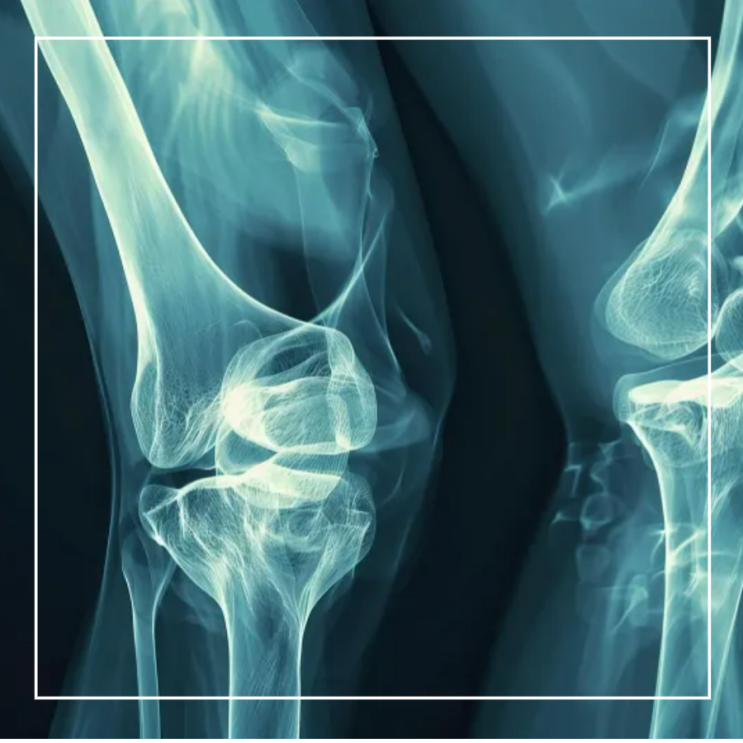

호관원 프리미엄 가격 및 효과 총정리: 중년 건강을 위한 완벽한 선택

안녕하세요! 호관원 프리미엄 가격 및 효과에 대한 새로운 시각을 나누고 싶어요. 오늘 소개드릴 내용이 특...